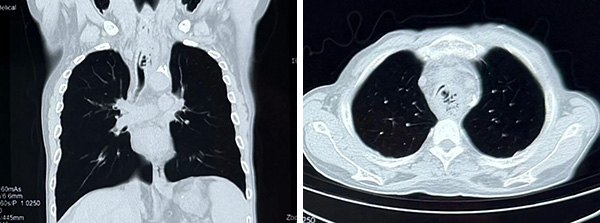

CT可见气管中段管腔严重狭窄伴食管纵隔瘘(左图为矢状位,右图为冠状位)

“气道狭窄程度极高,患者无法脱离氧气,必须立即置入气道支架解除梗阻!”,王洪武主任没有丝毫迟疑,当即表示接受患者转院治疗,并指示呼吸道梗阻抢救绿色通路,同时火速赶往医院。随即通知麻醉科医师王海丽、呼吸科二区值班医师张艳宾做好接收准备,备班医师陈双、护士赵行健及进修医师山萌在接到通知后,均毫不犹豫放弃假期,即刻动身赶往医院集结。W先生及家属赶到急诊室后立即办理住院手续,并快速送到门诊手术室进行抢救。